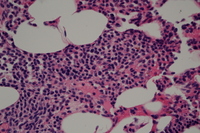

Mast cell nodular deposit in bone marrow with  mast cells showing elongated folded nuclei.